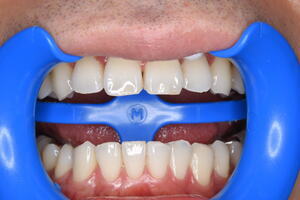

技工士がハンドメイドで作成したものには劣る(適合、形態)

装着が煩雑でフロスが引っ掛かるケースが多い(歯科医師のテクニカルエラー)